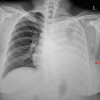

Pemasangan kateter interkostal (chest tube) atau yang dikenal juga sebagai prosedur tube thoracostomy bertujuan untuk melakukan drainase udara atau cairan dari kavum interpleura. Tindakan ini sering dilakukan pada kasus pneumothorax, hemothorax, efusi pleura, empiema, dan chylothorax.

Adanya udara atau cairan dalam kavum interpleura dapat menghambat ekspansi paru saat bernapas, sehingga pasien dapat mengalami sesak napas atau bahkan hipoksia. Pemasangan kateter interkostal dapat mengembalikan tekanan negatif intrapleura, sehingga paru dapat kembali mengembang dengan leluasa.